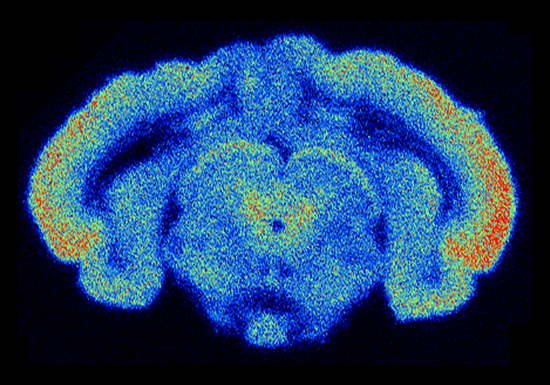

Figure 11.1: Différentes techniques d'histologie moléculaire appliquées à l'étude de la transmission cholinergique du cerveau de rat (au niveau du thalamus médian, Bregma -2.5 à -3.6 mm). De haut en bas et de gauche à droite: hybridation in situ à l'aide d'un oligonucléotide complémentaire de l'ARNm codant pour la sous-unité $\alpha $7, liaison de [125I]-$\alpha $-bgt, hybridation in situ à l'aide d'un oligonucléotide complémentaire de l'ARNm codant pour la sous-unité $\alpha $4, hybridation in situ à l'aide d'un oligonucléotide complémentaire de l'ARNm codant pour la sous-unité $\beta $2, liaison de [3H]-nicotine, révélation de l'activité cholinestérase par la méthode de KOELLE, liaison de [3H]-pirenzepine révélant les récepteurs muscariniques de type 1, liaison de [3H]-AFDX384 révélant les récepteurs muscariniques de type 2. Photos originales courtoisement procurées par Michele ZOLI

Sur la figure 11.1, trois techniques de neuro-anatomie chimique permettent de mettre en évidence les caractéristiques anatomiques principales de la transmission cholinergique à un niveau particulier du cerveau. On voit que les ARN messagers codant pour la sous-unité $\alpha $7 du récepteur nicotinique de l'acétylcholine sont distribués de manière très similaire aux sites de liaison de l'$\alpha $-bgt. En revanche les sites de liaison de la nicotine correspondent plutôt aux ARN messagers codant pour la sous-unité $\alpha $4 (eux-mêmes présent dans un sous-ensemble des structures exprimant la sous-unité $\beta $2). Ces différentes distributions ne correspondent pas à l'activité de l'acétylcholine estérase, supposée refléter l'activité cholinergique du tissu. La raison en est l'existence d'une autre population de récepteurs de l'acétylcholine, les récepteurs muscariniques. Les deux grandes classes de récepteurs muscariniques sont ici révélées par la liaison de pirenzépine (M1) et de AFDX384 (M2). Un autre exemple pourra être trouvé dans [373] où l'hybridation in situ et l'autoradiographie réceptorielle sont combinées avec l'électro-physiologie dans des animaux transgéniques afin d'étudier les différents types de récepteurs nicotiniques présents dans le cerveau.